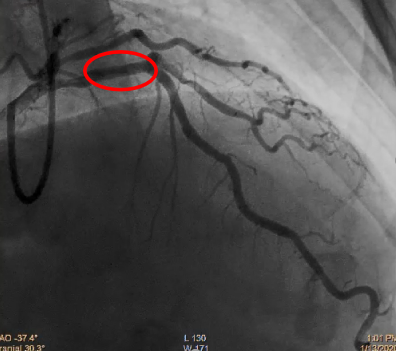

送入3.5-15mm药物涂层球囊RESTORE DCB 至p-mLAD病变处,到位时间40秒,扩张至10ATM(球囊直径3.65mm),持续时间46秒;DCB治疗后残余狭窄10%,TIMI血流3级。

介入治疗——DCB治疗术后

继续观察5分钟,复查冠脉造影未见夹层及弹性回缩,患者未诉不适,生命体征平稳。

介入治疗术前、术后对比

术后残余狭窄10%